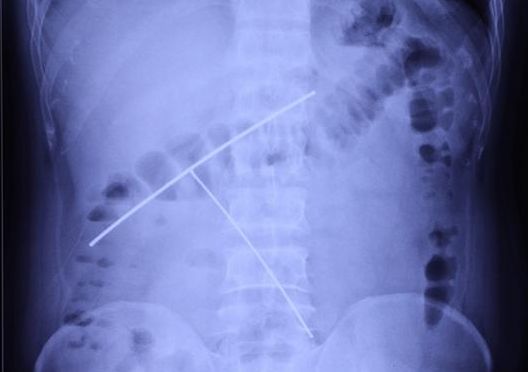

男子腹部X線影像

患者謝仕(化名)是常德市安鄉(xiāng)人,一直在外地從事魔術(shù)表演工作。4個月前,他在進行魔術(shù)表演“吞鋼絲”時,不慎將兩根鋼絲吞入腹中。因鋼絲曾被他用塑料管包裹,中間用軟線連接,當(dāng)時并未感覺到任何不適,并且他曾經(jīng)在上海演出時,也發(fā)生過一次類似意外事件,故而并未在意,未及時就醫(yī)。直到幾日前回到常德,突感腹痛不適,才到當(dāng)?shù)蒯t(yī)院就診。因異物為細長的鋼絲,呈倒T字分別位于胃及十二指腸部位,且在體內(nèi)停留時間長達4個月,內(nèi)鏡下取異物風(fēng)險及難度極大,必要時需要外科手術(shù)才能取出。為求進一步治療,遂來湘雅常德醫(yī)院消化內(nèi)科求醫(yī)。